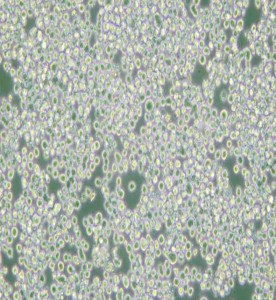

RPMI 8226人多發(fā)性骨髓瘤外周血B淋巴細(xì)胞

中文名稱 :人多發(fā)性骨髓瘤外周血B淋巴細(xì)胞

細(xì)胞簡(jiǎn)稱 :RPM I8226

細(xì)胞形態(tài) :淋巴母細(xì)胞樣

生長(zhǎng)特性 :懸浮細(xì)胞